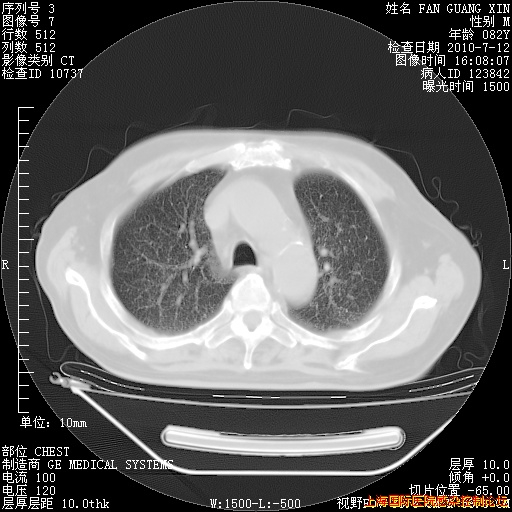

6月12日肺窗

今天复查CT

整整相隔30天的肺部CT好像有所好转啊。甲强龙减量第3天,需要观察体温。